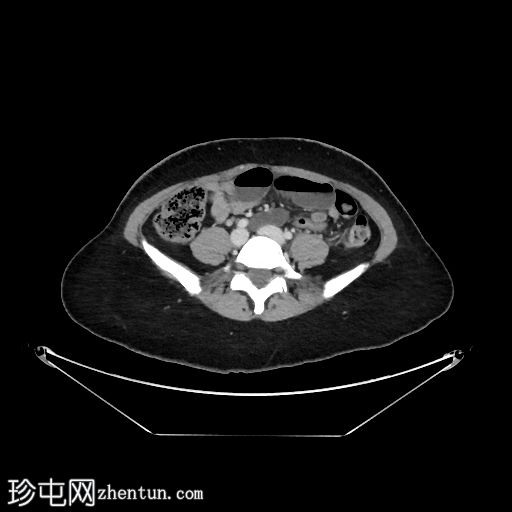

4.jpg

矢状位增强扫描(门静脉期)

多处回肠袢扩张,最大直径约3.3厘米,累及约46厘米肠段

可见两个移行区,一个位于近端,一个位于远端,扩张肠段位于两者之间

部分扩张肠袢肠壁强化减弱,提示肠缺血

远端移行区附近可见肠系膜血管呈旋涡状,即“漩涡征”

道格拉斯窝和子宫膀胱窝内可见少量盆腔游离液体

CT典型表现包括扩张的充满液体的肠袢、肠系膜血管扭曲形成的“漩涡征”,以及肠壁增厚、肠系膜水肿或腹水等。这种肠袢形态具有较高的缺血和绞窄风险,如不及时治疗,可能导致肠坏死。